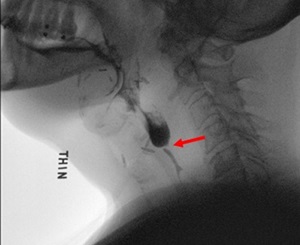

| Before Esophageal Dilation Example | After Esophageal Dilation Example |

|---|---|

![]() |